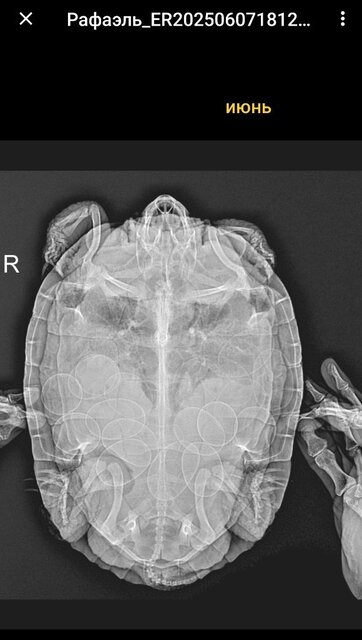

Но сегодня она при мне снесла яйцо без скорлупы, просто в оболочке. Питание основа рептамин, рыба/насекомые раз в месяц. УФ Рептиспа 10 увб 26вт работает 6,5 месяцев. На днях поставила новые уф. По анализам, которые сдавали 2 месяца назад, черепаха здоровая. Была задержка с выходом яиц, тк из в два раза больше,чем прошлые кладки, и на всякий случай прокололи курс на кальция 10 уколов месяц назад по рекомендации врача. Второй рентген в этом году было 19 яиц перед уколами кальция, после него уже вышло 27 яиц.

@Sonya5555 интересно, что по рентгену яиц нет, а по узи есть. Если только они там такие же без скорлупы.

А по структуре костей нет описания о дефиците кальция? я к сожалению не умею в этой области снимки читать.

@moth скорее всего да, тоже безскорлупные. Про структуру костей завтра уточню у рентгенолога, спасибо!